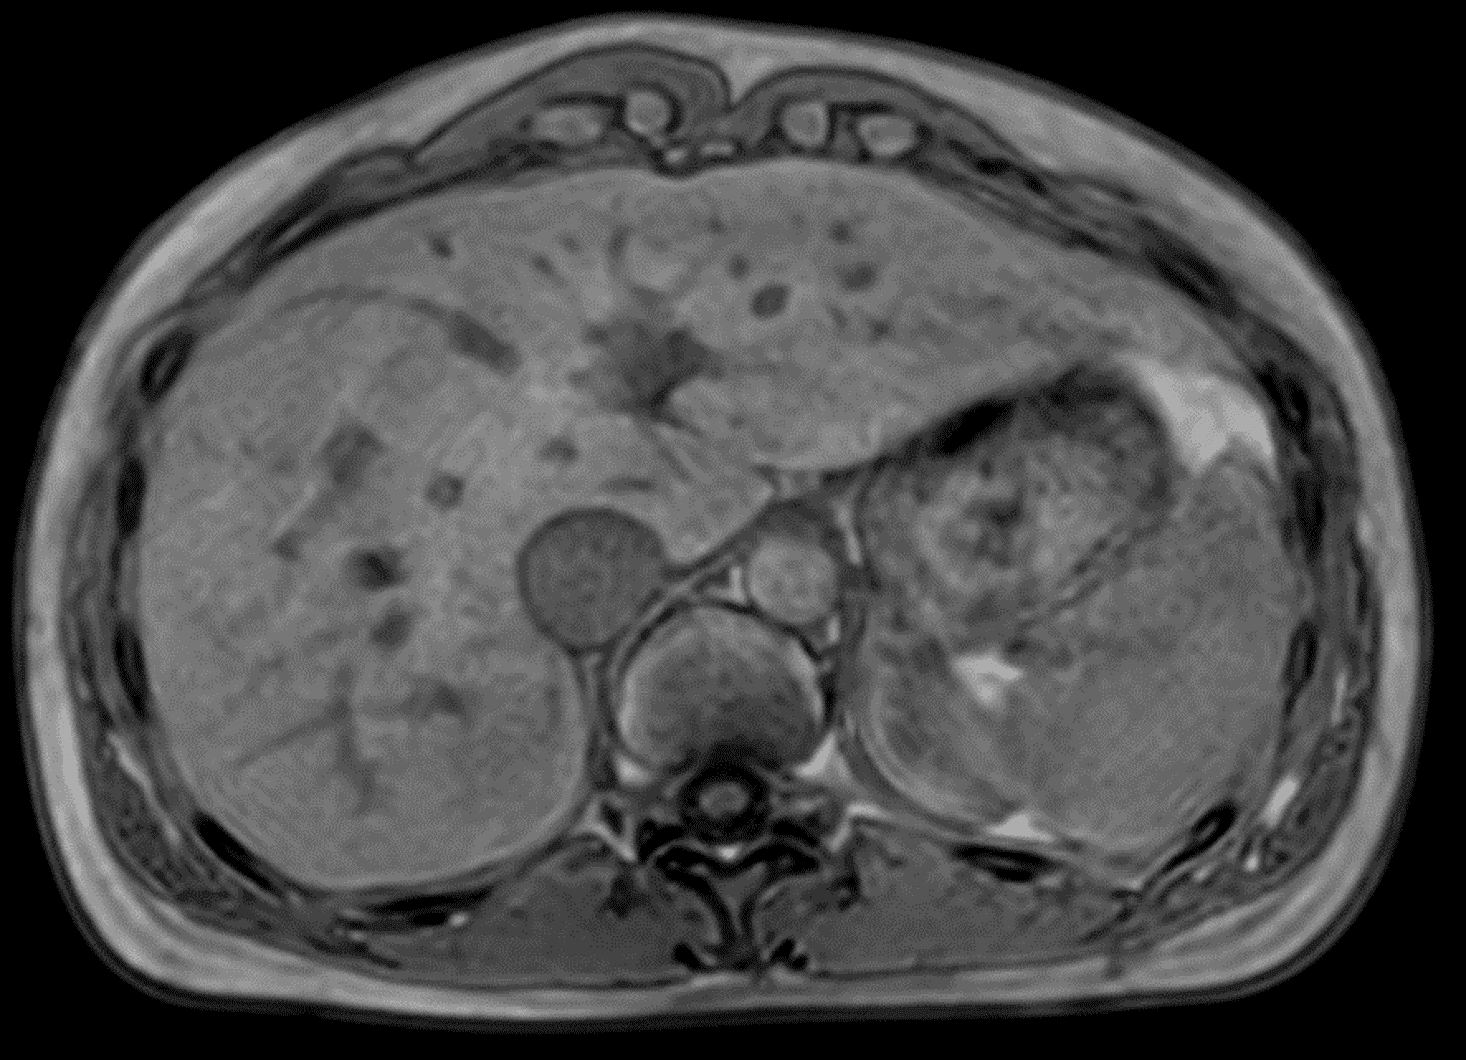

MRgRT, on the other hand, remains indispensable for more challenging cases where soft tissue contrast, real-time imaging, or functional imaging is critical. For example, in liver, pancreas, or rectal cancers, MRgRT enables visualization of structures that are poorly defined on CT, or in cases with mobile tumors, Elekta Unity with real time motion monitoring allows safe delivery of ablative doses.